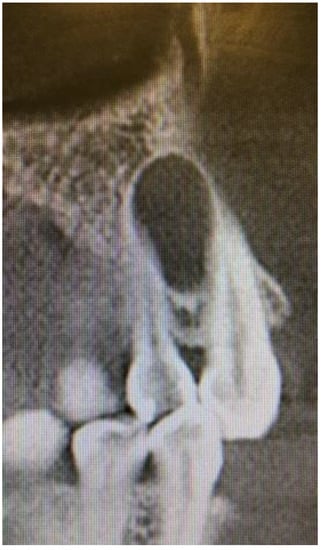

A 35-year-old female patient presented with a small, well-defined lesion on the attached gingival area, approximately 5/6 mm in diameter between roots of teeth 23–24, reported to the Privat Dental Clinic. The patient’s main concern was focused on gingival asymmetry and a tumor-like mass, painless and sometimes tender on tooth brushing. Clinical anamnesis revealed the occurrence of this asymptomatic mass for over 6 months. Because of swelling and atypical cortical expansion, the patient was referred for consultation and treatment. The patient was generally healthy without any chronic illness or important medical and dental past. A routine panoramic radiograph revealed a well-defined, radiolucent, left maxillary lesion located between the roots of the canine and first maxillary premolar (Figure 1 and Figure 2).

Figure 1. Panoramic radiograph slice from CBCT evaluation of LPC.